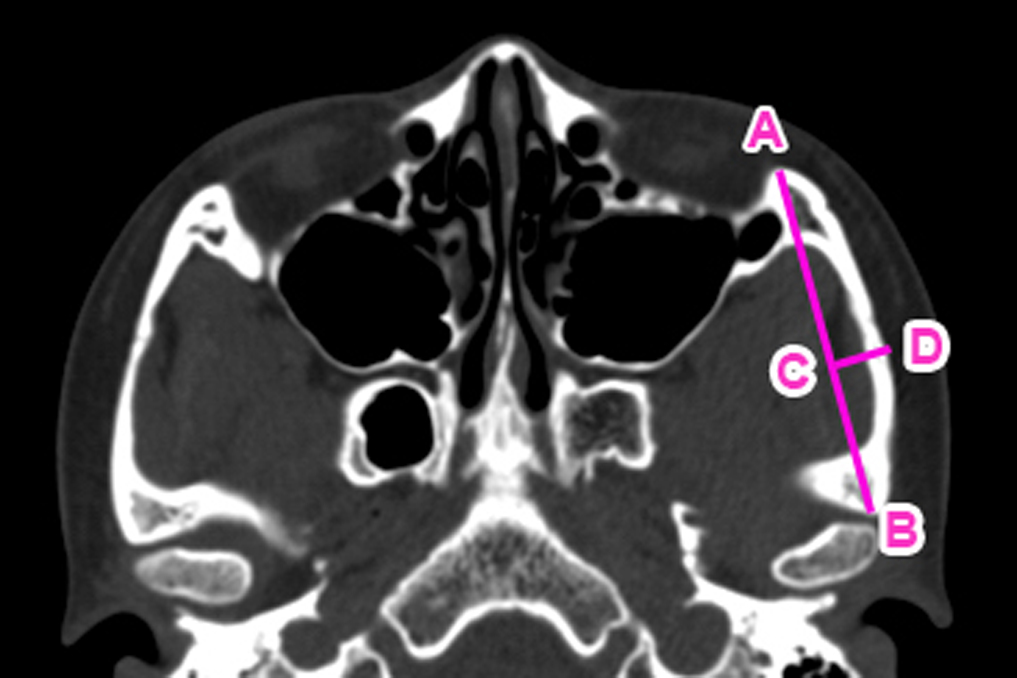

采用数字化CT影像评估患者颧弓外突程度。测量及计算的参数和标志如下(见图1):在颧弓横断面CT影像中,自颧弓前根(A点)至后根(B点)连线代表颧弓弦长。标记颧弓最外突点(MPP,D点),其至弦线的垂直距离(D点至C点)即为颧弓高度(HOA)。前根至最突点距离(ARMPPD)为A点至D点距离,后根至最突点距离(PRMPPD)为B点至D点距离。

图1. 颧弓突出几何学评估所用的标记与参数。A–B 线表示颧弓的弦长,C–D 线表示颧弓的高度(HOA)。